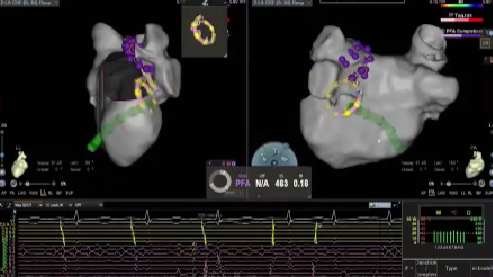

VARIPULSE作为首款搭载Carto三维平台的脉冲消融产品,自上市以来,凭借其“高效”、“绿色”与“贴靠”三大核心价值,赢得了国内专家的广泛认可。上市百日内,已成功服务近七百位中国患者,实现近100%的即刻手术成功率,平均消融时间仅35分钟,且超过20%的手术在零射线条件下完成。凭借这一卓越的临床表现,VARIPULSE不仅为医疗工作者提供了更先进、更全面的治疗方案,也为广大患者带来了恢复窦性心律的新希望。

在本次电生理手术直播周期间,20位资深术者通过实时手术演示,全方位展现了 VARIPULSE脉冲消融系统在房颤治疗中的高效与绿色优势,将其临床性能推向极致。手术数据亮眼——全场直播的平均消融时间仅28分钟,充分印证了该系统的高效性;学术交流同样热烈,超50位领域专家齐聚线上,围绕‘麻醉方案优化’‘、“术式创新选择”、”并发症预防策略”等脉冲电场消融领域的核心热点话题,展开深度研讨与观点碰撞。

VARIPULSE在心房较大房颤患者中,无论是在建模还是贴靠上都具有优势,导管偏硬的设计,保证了良好的贴靠,帮助术者在术中更好的判断贴靠情况,同时TPI的加持使得VARIPULSE的隔离效率非常高。